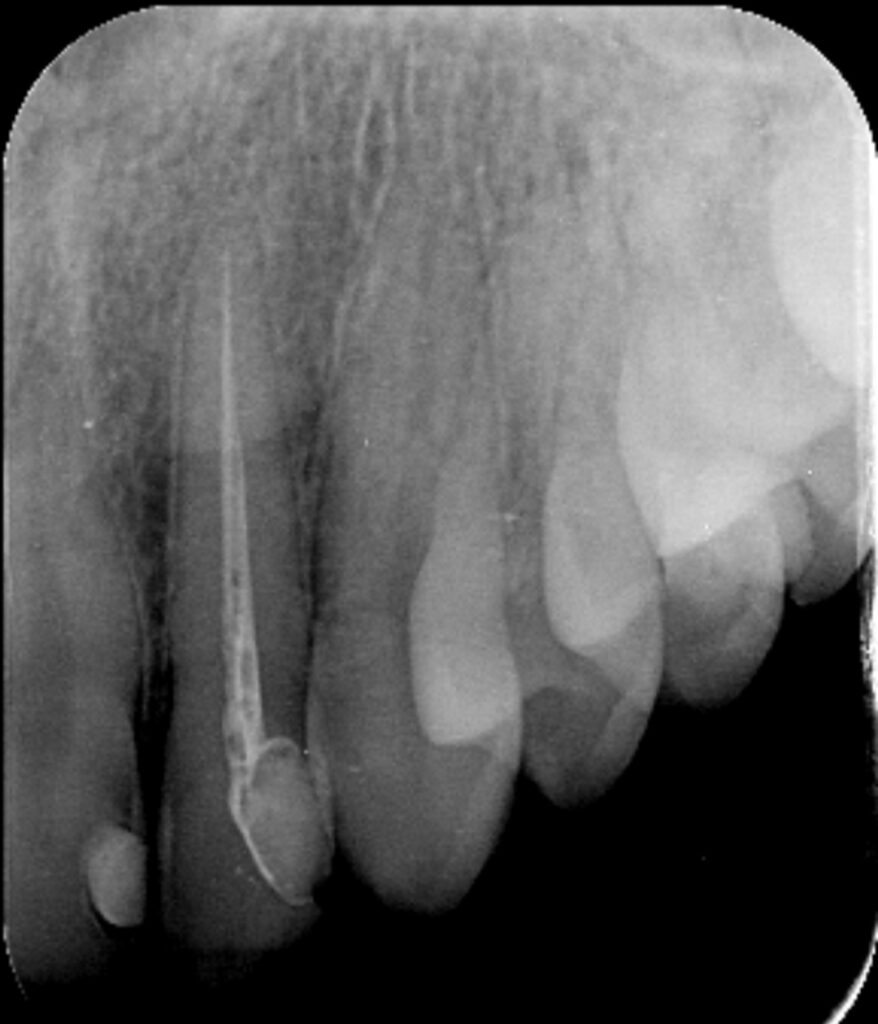

- Lečenje kanala korena zuba(endodoncija)

Konzervativna stomatologija je grana stomatologije koja obuhvata bolesti zuba i endodonciju. Najčešći uzrok nastanka oboljenja zuba je zubni karijes. U zavisnosti od stepena rasprostranjenosti karijesa u zubnim tkivima, zavisiće i sam tok terapije. Ukoliko karijes nije zahvatio „zubni živac“ ili pulpu zuba, plan je preparisati kavitet i postaviti ispun koji se još u narodu zove plomba. Ukoliko karijes jeste zahvatio pulpu zuba, plan je ekstirpirati(izvaditi) „živac zuba“, adekvatno obraditi kanale i nakon toga napuniti ih gutaperkom i silerom.